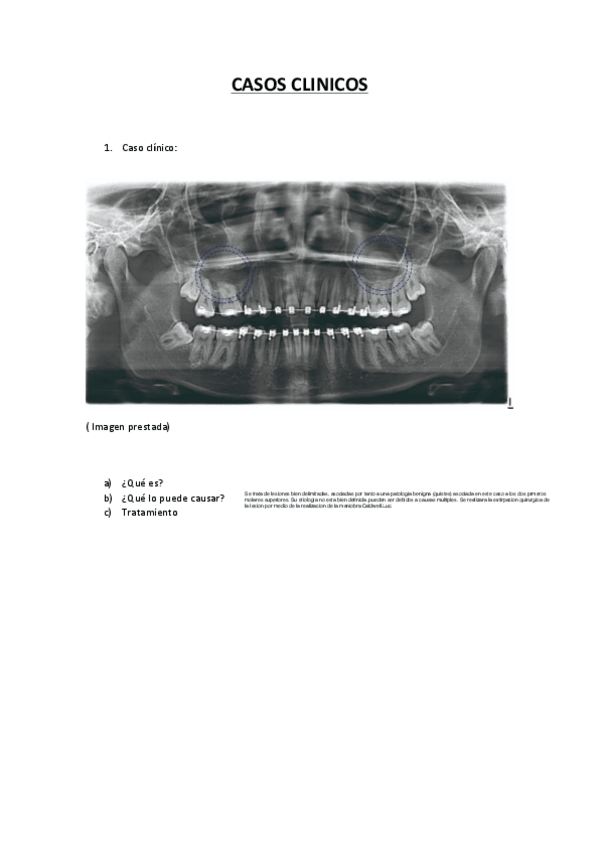

CASOS CLINICOS REPASO

He publicado nuevos ejercicios de 5º CLÍNICA INTEGRADA II: CASOS CLINICOS REPASO